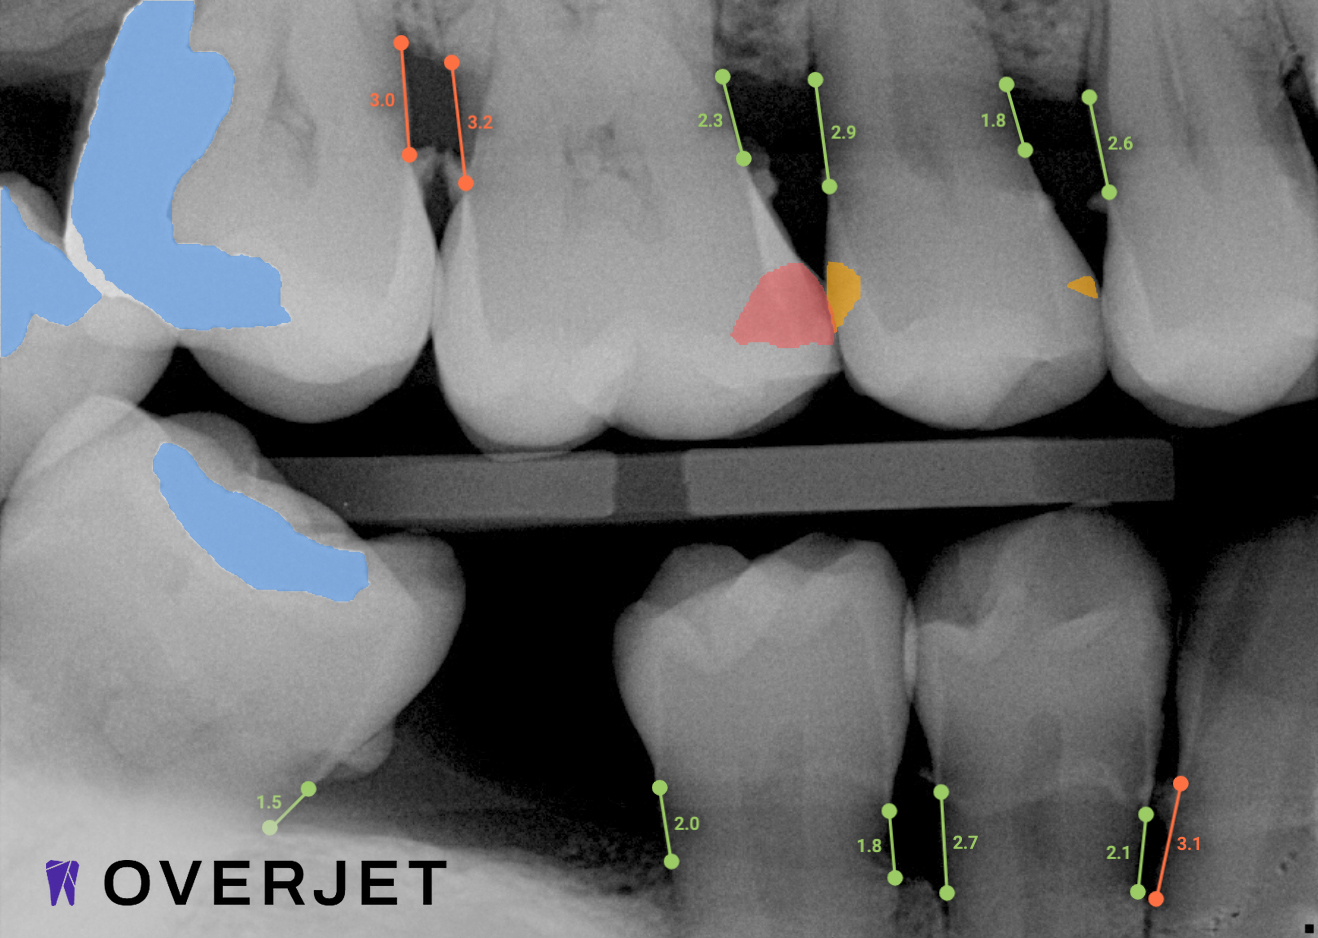

Our practice is proud to provide the best technology in the dental industry, including Overjet AI for instant X-ray analysis.

Overjet’s artificial intelligence technology transforms traditional black-and-white X-rays by adding a layer of data that instantly outlines decay (cavities) and measures bone loss. This makes it easy for you to see your results alongside your dentist.  It’s like getting a second opinion delivered instantly. With Overjet’s analysis and easy-to-read presentation, you will have the information you need to make an informed decision about your oral health. Together, we’ll review your findings and discuss the best steps to take to achieve your goals.